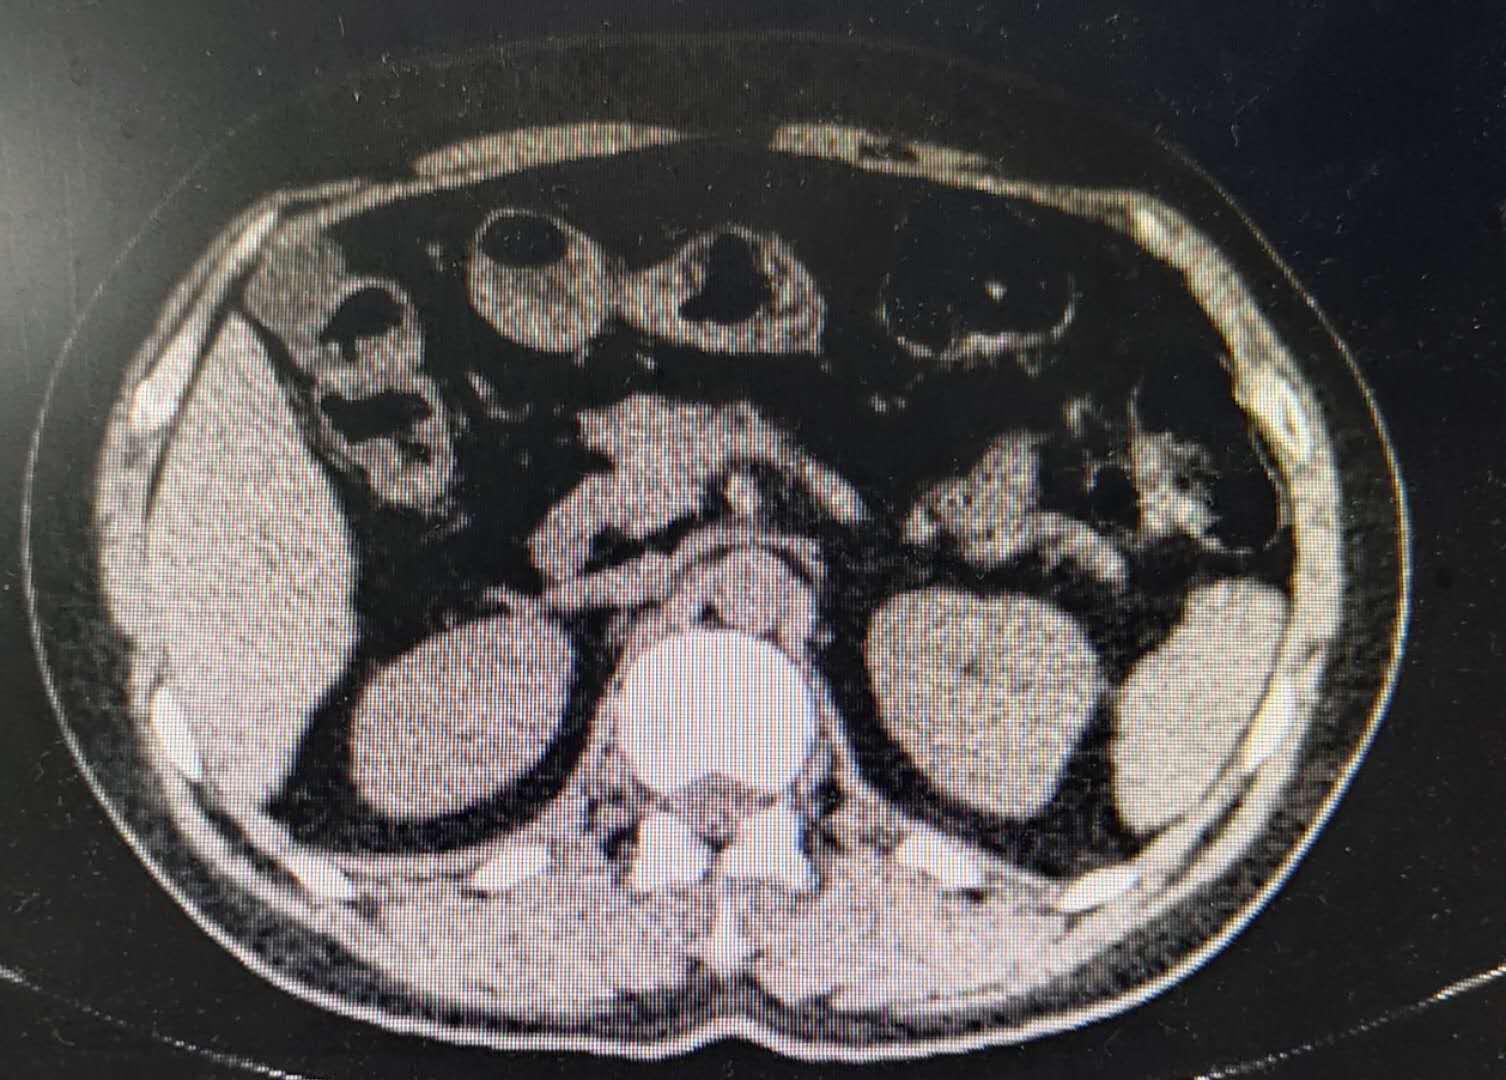

第一次见到患者是在九年前,当时她才46岁,接诊患者时她告诉我从上次月经来潮到现在经血一直淋漓不断已经1个多月了。在做专科查体时我发现她的宫颈外口已经被一个约7cm×6cm大小的菜花状组织堵塞了。B超检查提示宫颈低回声肿物,高度怀疑宫颈癌(图1)。盆腹腔CT检查提示子宫正常大小,宫颈增粗内可见低回声团7cm×6cm,双侧髂血管旁、腹股沟取可见多发稍大淋巴结(图2)。后进一步做宫颈肿物活检病理,病理结果显示为低分化鳞状细胞癌。患者入院时被诊断为宫颈鳞癌ⅡA2期。

图2 盆腹腔CT检查显示宫颈增粗,内可见低回声团。